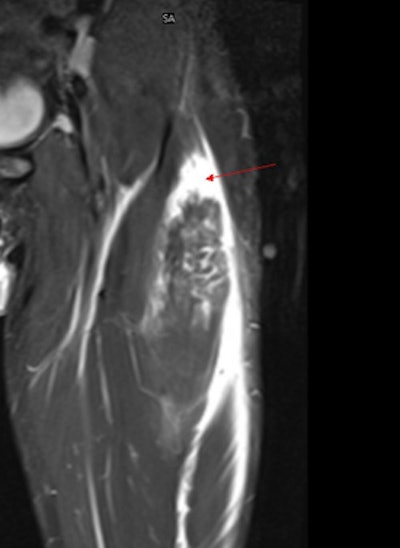

Remote clinical specialists such as musculoskeletal (MSK) and neuroradiologists can then quickly review the images and, if needed, send an embedded annotated image -- saved and indexed alongside the original scan, together with their online report. For the player, the club, and the club doctor, the key advantage is rapid access to specialist sports medical opinion. In addition, the system allows clubs to create a comprehensive club archive of all their diagnostic images that can be sent online from the imaging centers or imported from CDs.